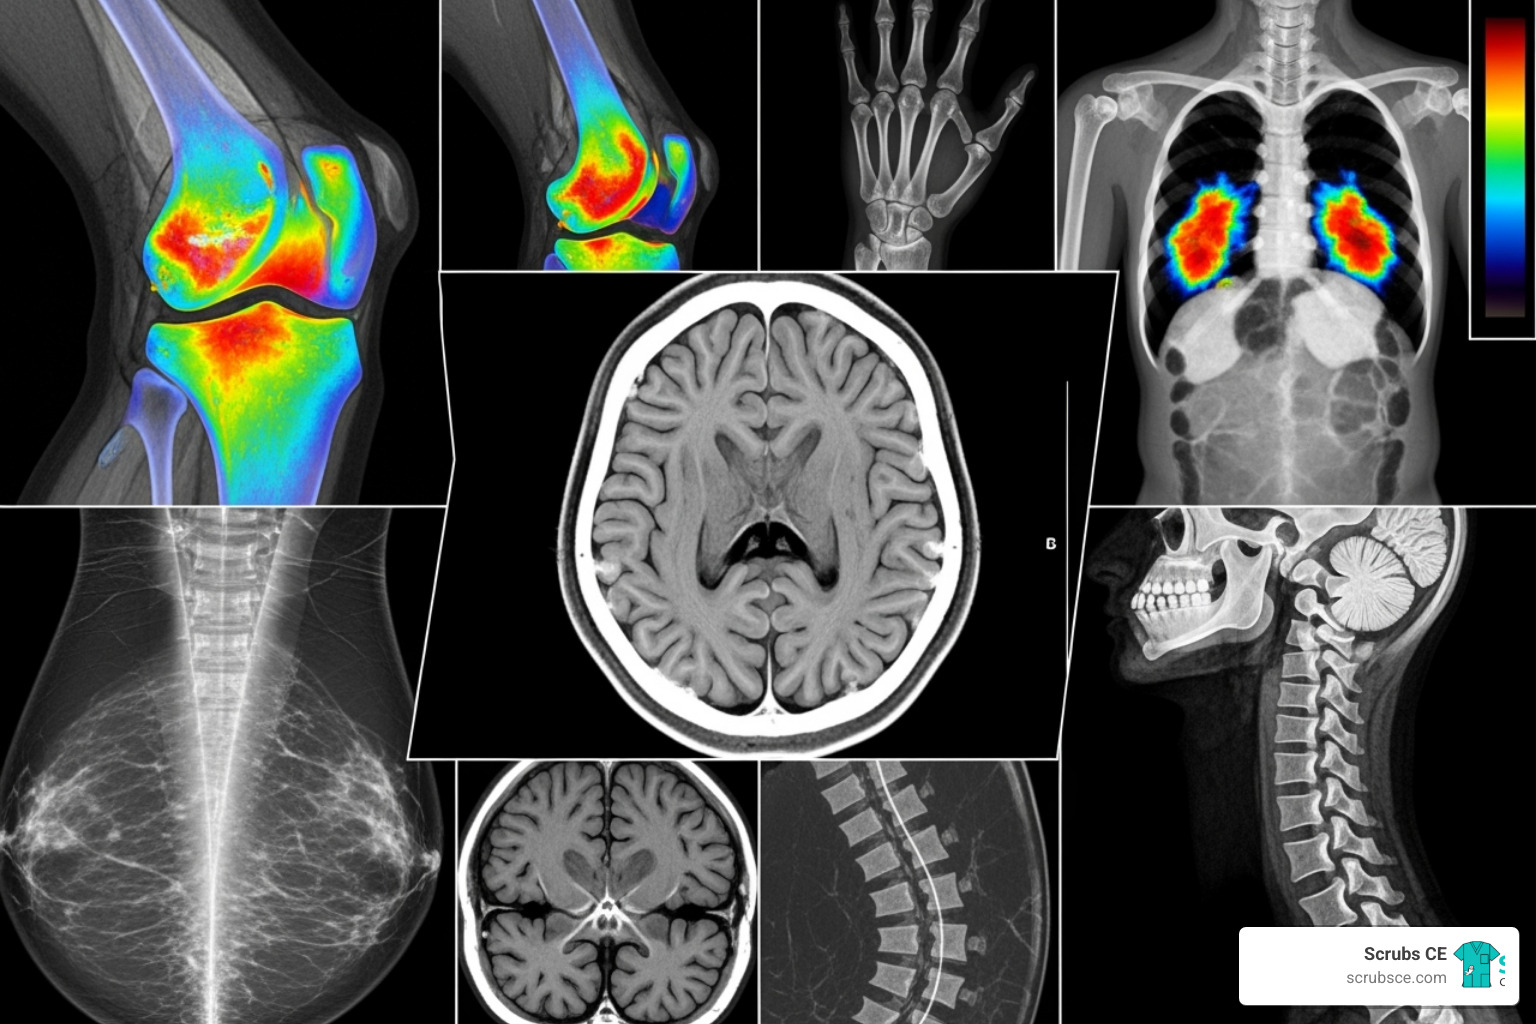

Radiology ce courses are accredited programs that help imaging professionals maintain ARRT® certification, meet state licensure requirements, and advance their careers. These courses cover specialized topics across modalities like X-ray, CT, MRI, and mammography.

Most radiology ce courses focus on specific imaging modalities, allowing you to build expertise or branch into a new area.

- X-Ray (Radiography): Courses cover positioning, physics, and advanced digital techniques. We offer 21 X-Ray courses for $39.99. Explore our Continuing Education Courses for X-Ray Technologists.

- Computed Tomography (CT): Dive into advanced protocols, 3D reconstruction, and image interpretation. We provide 15 CT courses for $35.00.

- Magnetic Resonance Imaging (MRI): Tackle MRI physics, advanced sequences, and specialized applications. Access 22 MRI courses for $39.99. For a full selection, visit CT/MRI CE.

- Mammography: Focus on screening techniques, breast pathology, and quality control. We offer 9 mammography courses for $29.99. See our Mammography CE Courses.

- Nuclear Medicine: Explore radiopharmaceuticals and SPECT/CT and PET/CT imaging. Find courses at Nuclear Medicine CE.

- Ultrasound: Cover diverse applications from abdominal to musculoskeletal imaging. Visit our Ultrasound CE Courses.

- Fluoroscopy: Focus on radiation safety and interventional procedures. See our Fluoroscopy CE Courses.